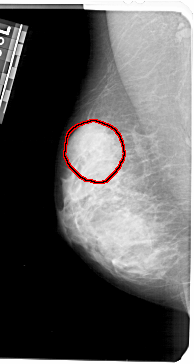

FILE: A_1353_1.LEFT_MLO.OVERLAY

TOTAL_ABNORMALITIES 1

ABNORMALITY 1

LESION_TYPE CALCIFICATION TYPE PLEOMORPHIC DISTRIBUTION SEGMENTAL

ASSESSMENT 4

SUBTLETY 2

PATHOLOGY BENIGN

TOTAL_OUTLINES 1

BOUNDARY